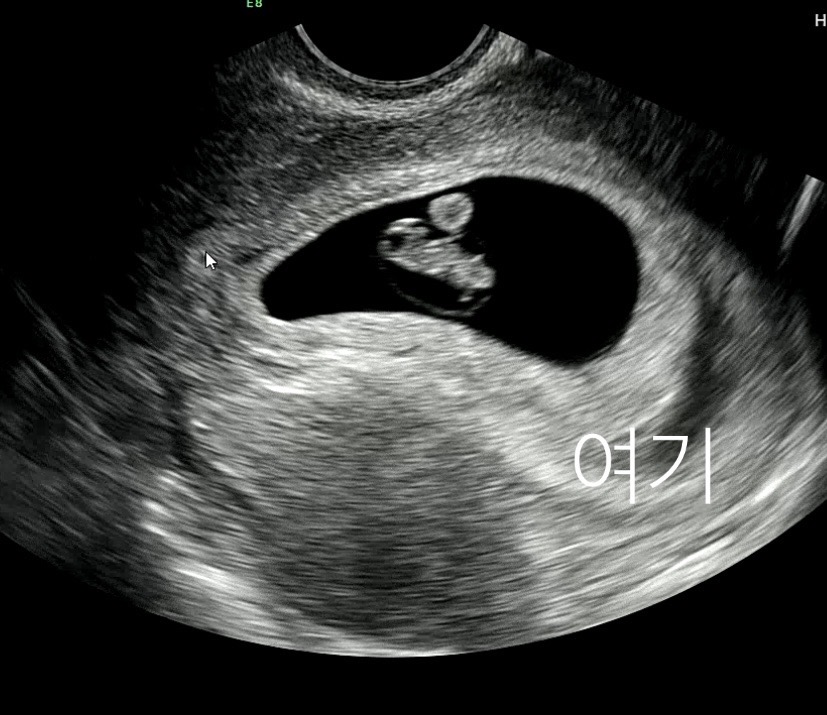

7주 피고임 생겼는데

다행히 아가는 잘크고 있고 심박수도 150회 넘더라고요 피비침이나 증상은 없는데 피고임 자연스럽게 사라질까요? ㅠㅠㅠㅠㅠ